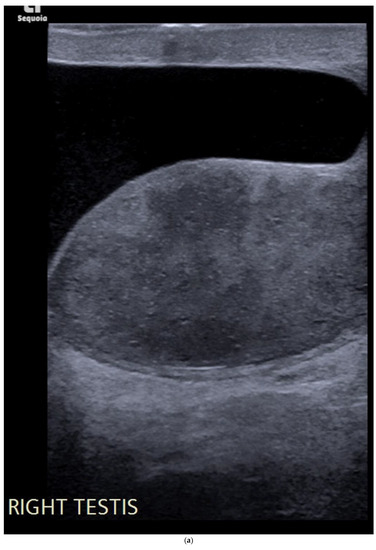

4.1. Seminomatous Germ Cell Tumour

| Seminomas | Homogenous and hypoechoic Well circumscribed Occasionally contain cystic components or calcifications |